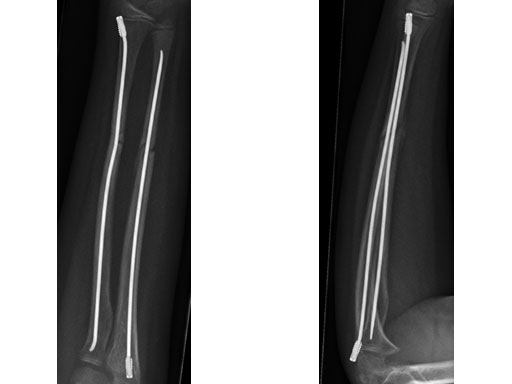

Case 2: Oblique forearm, shaft fracture (22D/5.1) with end caps, 11-year-old boy.

Case provided by Theddy Slongo, Bern, Switzerland